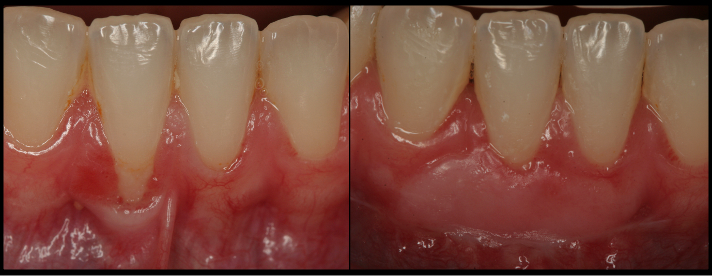

Cover receding roots and improve the esthetics and restorative outcomes.